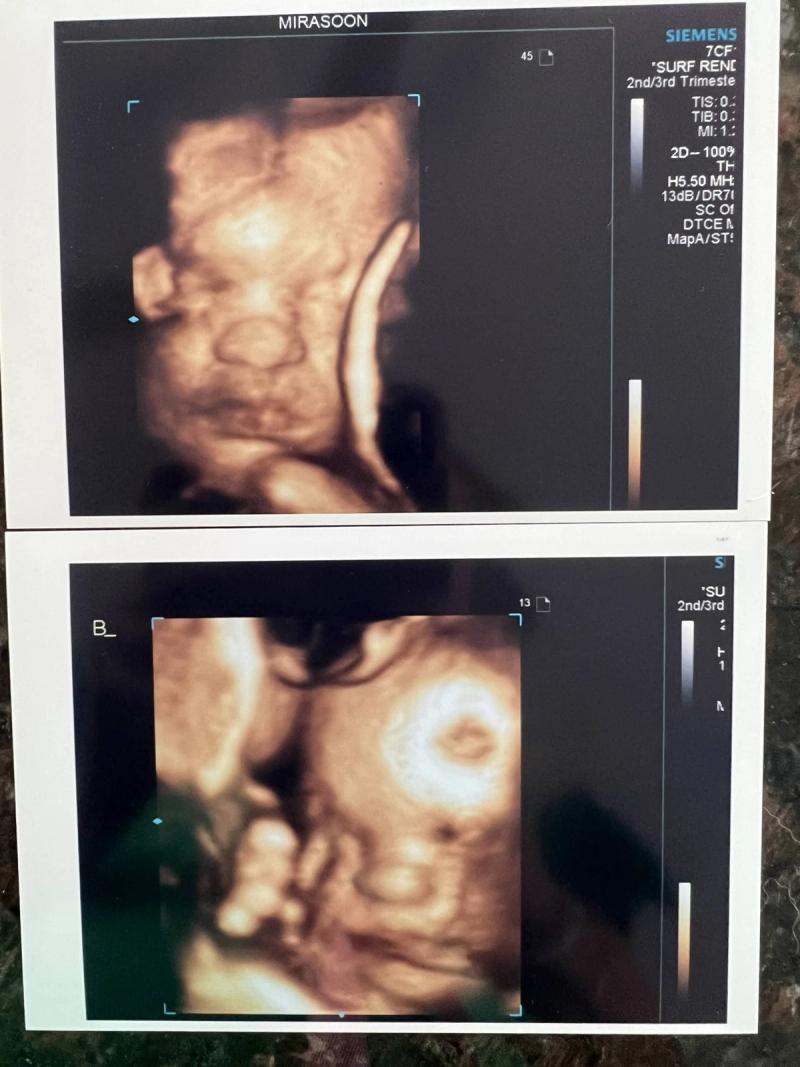

Zeker met alle risico’s die het tijdens de zwangerschap met zich meebrengt, de terror tijd van de newborn fase en alle fases erna. Als ik ergens hoorde dat iemand een tweeling verwachtte, dacht ik altijd van: “Pfoeh, nou… Súper leuk voor je, maar liever jij dan ik.” Dus nog groter is de ironie toen we op de echo niet 1 maar 2 kloppende hartjes zagen verschijnen. Niet alleen alle risico’s en mogelijke complicaties in mijn schoot geworpen, ook nog eens de gedachte van moeder zijn van 4 kinderen. HOLY MOLY.

Een eeneiige tweeling, die ook nog eens de placenta deelt en constant met elkaar in verbinding staat. Iets magisch. De eerste brieven over meedoen aan onderzoek vanuit het CBS zijn al ontvangen, want betere studies dan die onder eeneiige tweelingen zijn er eigenlijk niet te doen voor de wetenschap. En dan lees je ook dingen als: voor alle kinderen (ook twee-eiige tweelingen), zijn de ouders het meest belangrijk in het leven van het kind en heeft het overlijden van een van de ouders de grootste impact qua verlies die het kan kennen. Is dit voor een eeneiige tweeling een uitzondering. Daar is onderzocht dat de wederhelft het meest belangrijk is en de grootste impact zal hebben in geval van verlies. Een bizarre constatering. Hoe gaat die band zijn? En hoe gaat Vive het vinden als grote zus van een eeneiige tweeling?